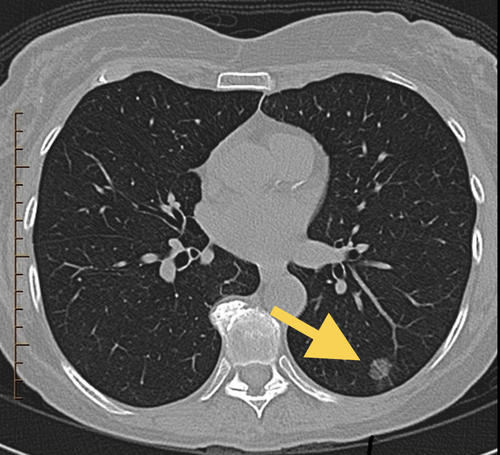

患者陈女士近日在单位体检中查胸部平扫CT时发现左侧肺部有一个直径约10mm的肺部纯磨玻璃样结节(如图,磨玻璃结节指:密度较低,在CT图像上像一块磨玻璃似的病灶)。

经过MDT团队中包括胸心外科、呼吸科、影像科、病理科等多门学科专家合作诊疗后,各位专家认为陈女士左肺的磨玻璃病灶直径较大,且病灶旁可见短小毛刺,病灶内部密度稍有不均,考虑早期肺癌可能性大,建议限期行手术切除,明确病理结果的同时进行外科手术治疗。